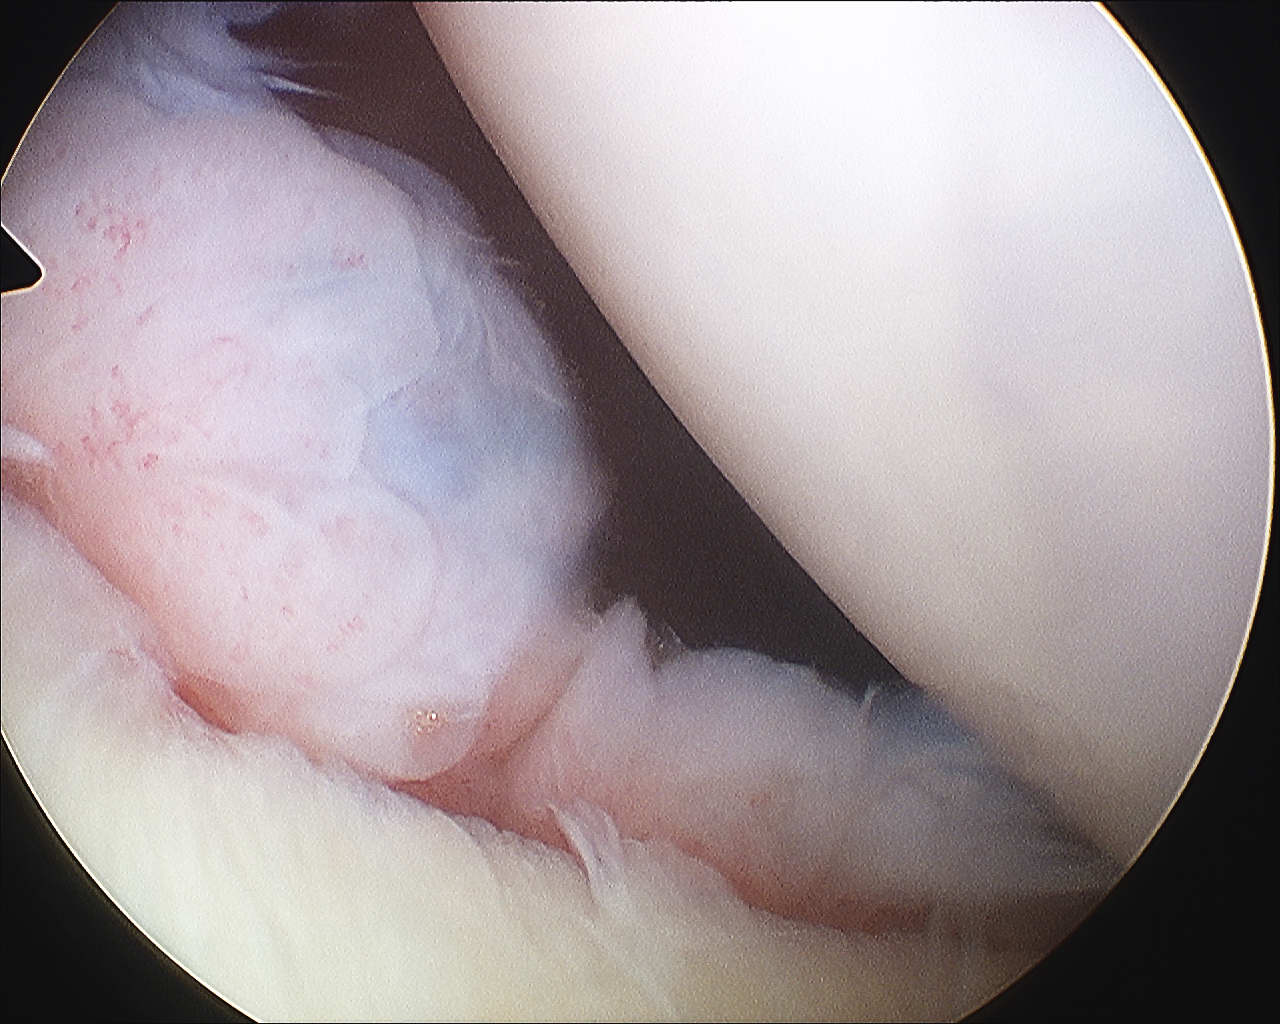

Glenoid assessment

Shoulder Anterior Glenoid Deficiency

Anterior chondral damage

Glenoid Bone LossGlenoid Bone Loss Measurement 1Glenoid Bone Loss Measurement 2

Anterior glenoid bone loss

Hill Sachs lesion

Hill Sachs ArthroscopyShoulder Engaging Hill SachsHill sachs